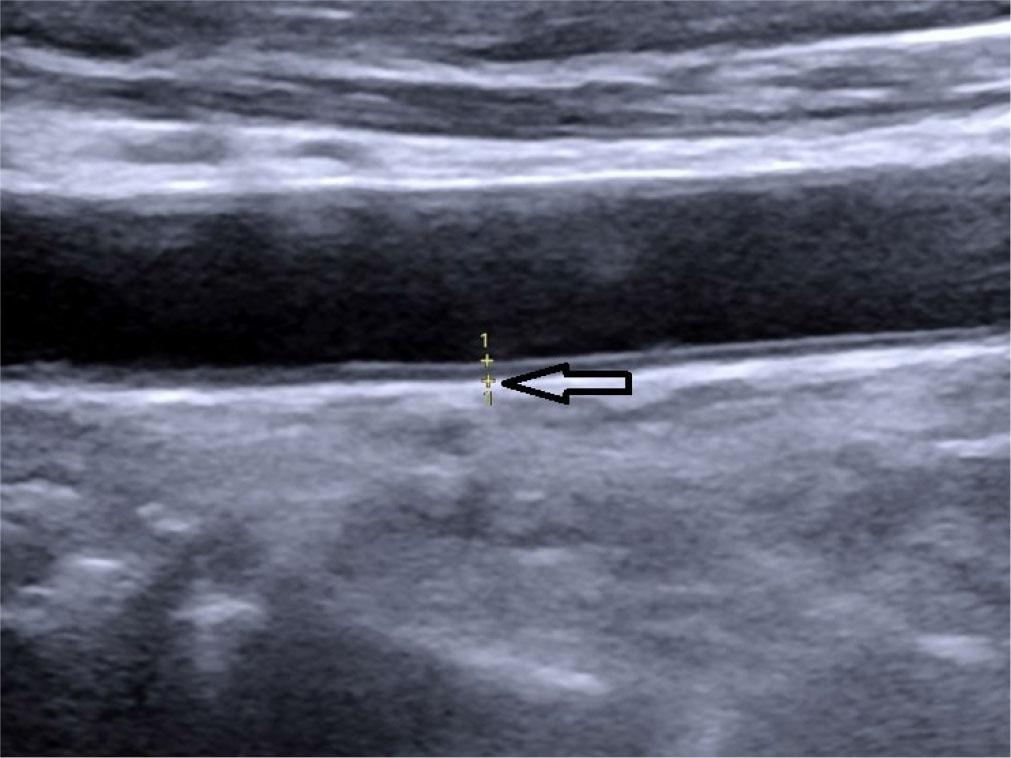

Intima-media thickness (CIMT) – the distance between the outer and inner borders of the double-line pattern in the far wall of the common carotid artery (CCA) observed in the longitudinal view during neck ultrasound. Five measurements were taken on each side, 1 cm proximal to the carotid bifurcation, and the average of the measurements was considered as CIMT for statistical analysis(25,26) (Fig. 6).

Oblique longitudinal grey scale ultrasound of the neck showing measurement of carotid intima-media thickness (CIMT) denoted by calipers, marked by hollow arrow (0.08 cm)